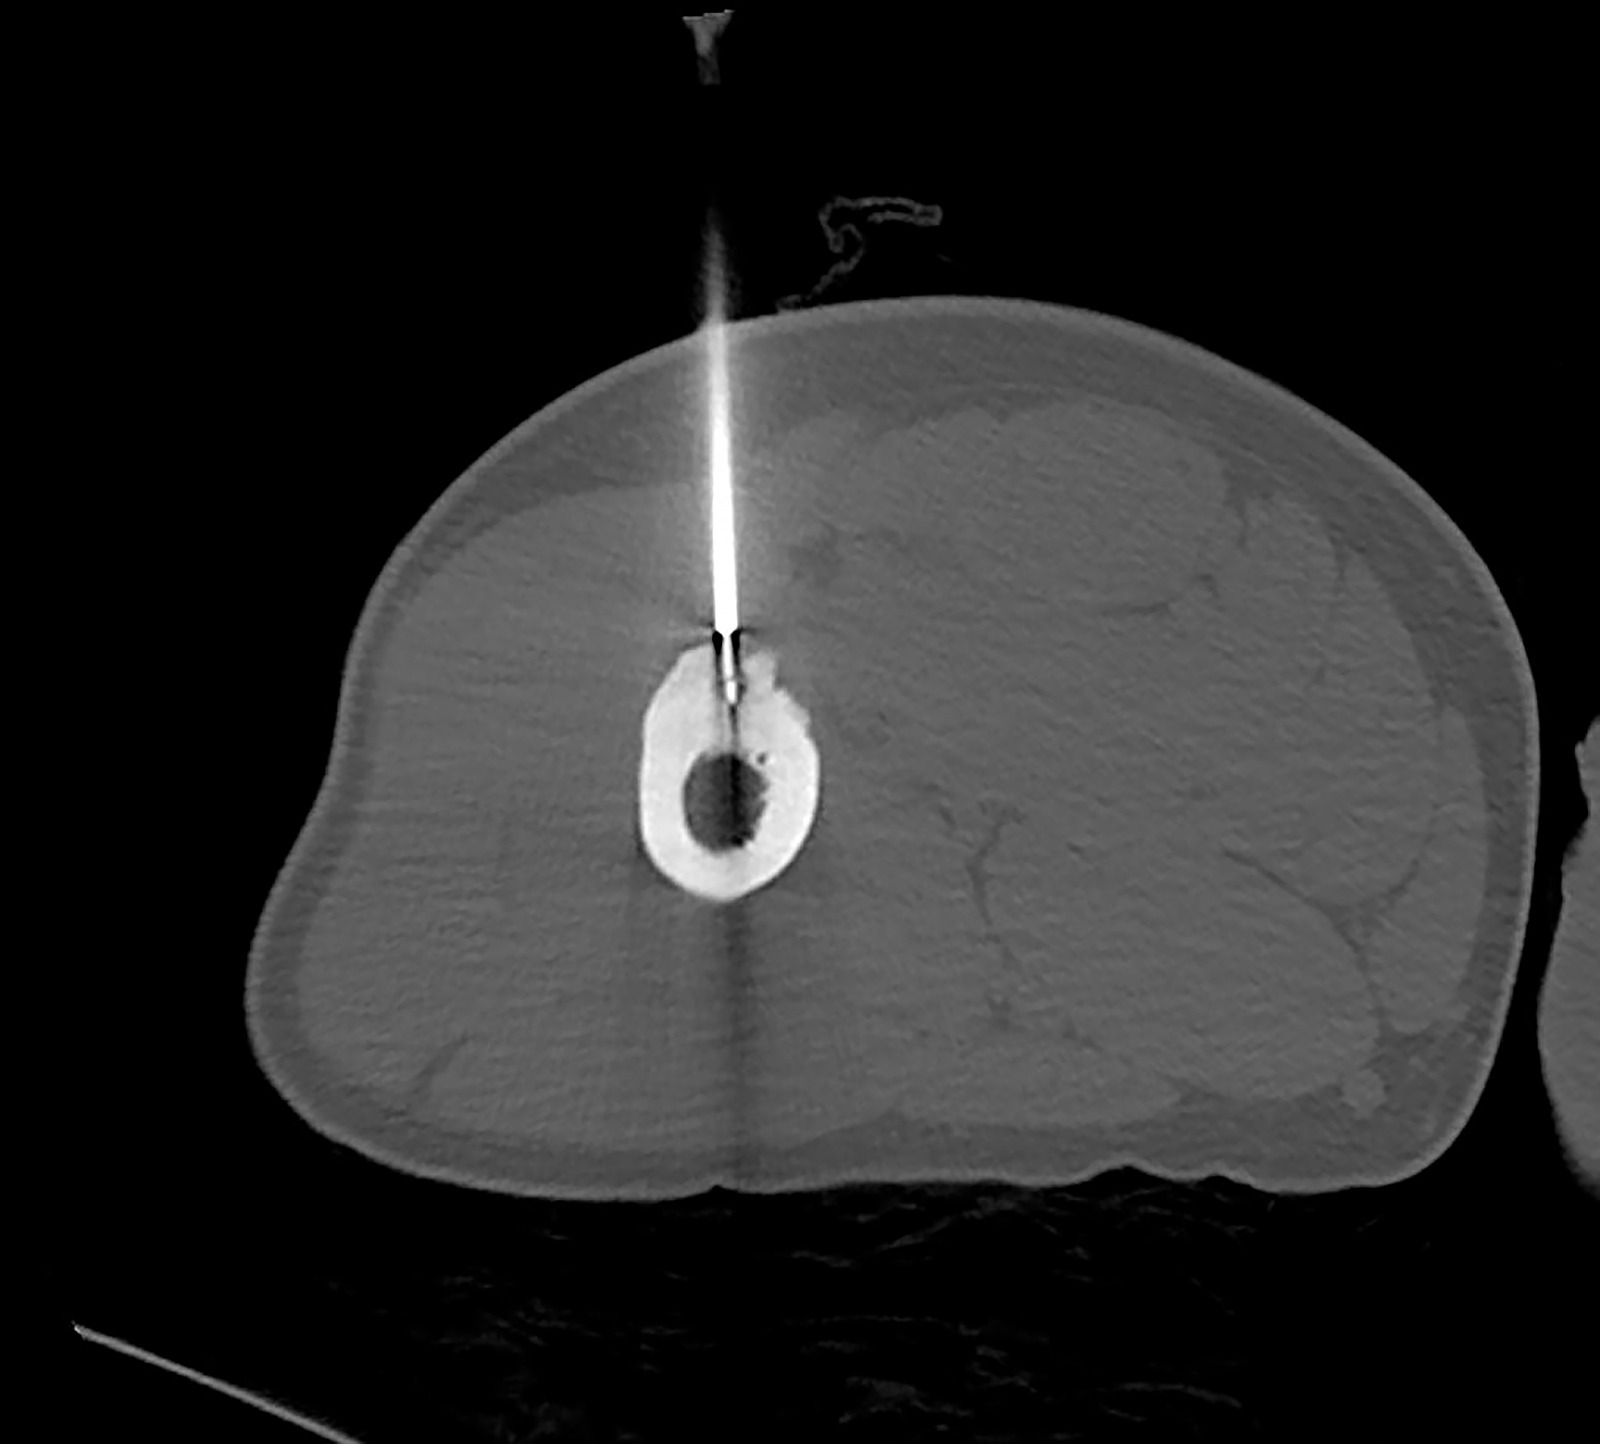

Operasyonla ilgili konuşan KSÜ Tıp Fakültesi Radyoloji Ana Bilim Dalı Öğretim Üyesi Doç. Dr. Nursel Yurttutan, şunları söyledi: “Hastamız aktif askerlik mesleğini yapan genç yaşlarda bir erkek. Uzun süredir var olan bacak ağrısı şikâyetiyle tetkik edilirken, uzuv kemiklerinden bir tanesinde küçük boyutta bir lezyon tespit edildi. Bu lezyon ‘osteoid osteoma’ adı ile bilinen iyi huylu bir kemik tümörü türü. Hastanın hayatını tehdit edici bir unsur değil ancak özellikle geceleri artan ağrı semptomu hastaların hayat kalitesini ciddi manada düşürmekte ve uzun süreli ağrı kesici kullanma ihtiyacı hastaları kronik dönemde ağrı kesici bağımlılığına sürüklemektedir. Bunun gibi bir takım kemik tümörlerinde cerrahi tedaviye alternatif olarak özellikle son yıllardaki tıp alanında hızlı gelişmeler sayesinde çeşitli uygulamalar yapılıyor. Biz hastamızda ‘radyofrekans ablasyon’ işlemini uyguladık. Bilgisayarlı tomografi eşliğinde milimetrik boyutta bir kesi alanından kılavuz iğnelerle girip milimetrik boyuttaki lezyon alanına komşu dokulara zarar vermeden ulaştık ve kemik tümörünü ‘radyofrekans ablasyon iğnesi’ ile yüksek ısıyla yaktık. KSÜ Tıp Fakültesi Ortopedi ve Anestezi Bölümlerinin desteği ile gerçekleştirdiğimiz işlemde genel anestezi ile uyutulmadan hastamızın sadece alt ekstremitelerine geçici olarak bölgesel anestezi ve analjezi uygulandı. Bir günlük takip sonrasında da hastamızı taburcu ettik. Literatürde bu işlemin teknik başarı oranının yüzde 95 ila 100 arasında olduğu bildirilmektedir. Üniversitemiz bünyesinde iyi huylu kemik tümörü tedavisi yanında uygun hasta gruplarında cerrahiye uygun olmayan ya da cerrahiye alternatif olabilecek çeşitli tümör tiplerinde radyofrekans ya da mikrodalga ile ablasyon işlemleri minimal invazif olarak, girişimsel radyoloji bölümü öğretim üyelerimiz tarafından gerçekleştirilmektedir.”